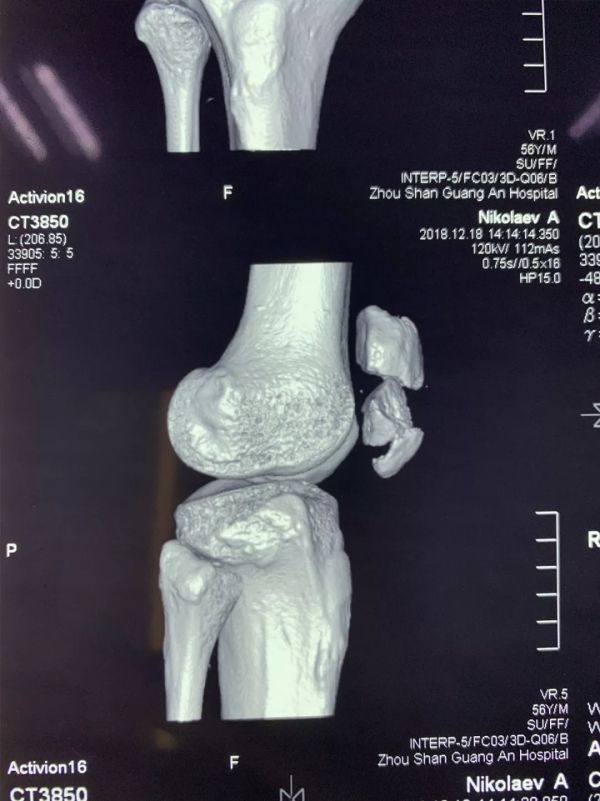

近日,廣安醫(yī)院關(guān)節(jié)科羅軍主任帶領(lǐng)科室團(tuán)隊(duì)成員為一名來(lái)自俄羅斯的患者成功施行了右髕骨粉碎性骨折切復(fù)內(nèi)固定手術(shù)治療,術(shù)后三天患者能自行起床活動(dòng)。

患者從遙遠(yuǎn)的俄羅斯來(lái)到美麗的舟山群島船廠指導(dǎo)工作,旅途中不慎跌倒,導(dǎo)致右髕骨粉碎性骨折,需行手術(shù)治療,患者來(lái)到廣安醫(yī)院就診,然而語(yǔ)言不通,患者只能聽(tīng)懂簡(jiǎn)單的英文,怎么辦?機(jī)智的易觀俊主治醫(yī)師用手機(jī)上的翻譯軟件,搭好了醫(yī)患溝通的橋梁。